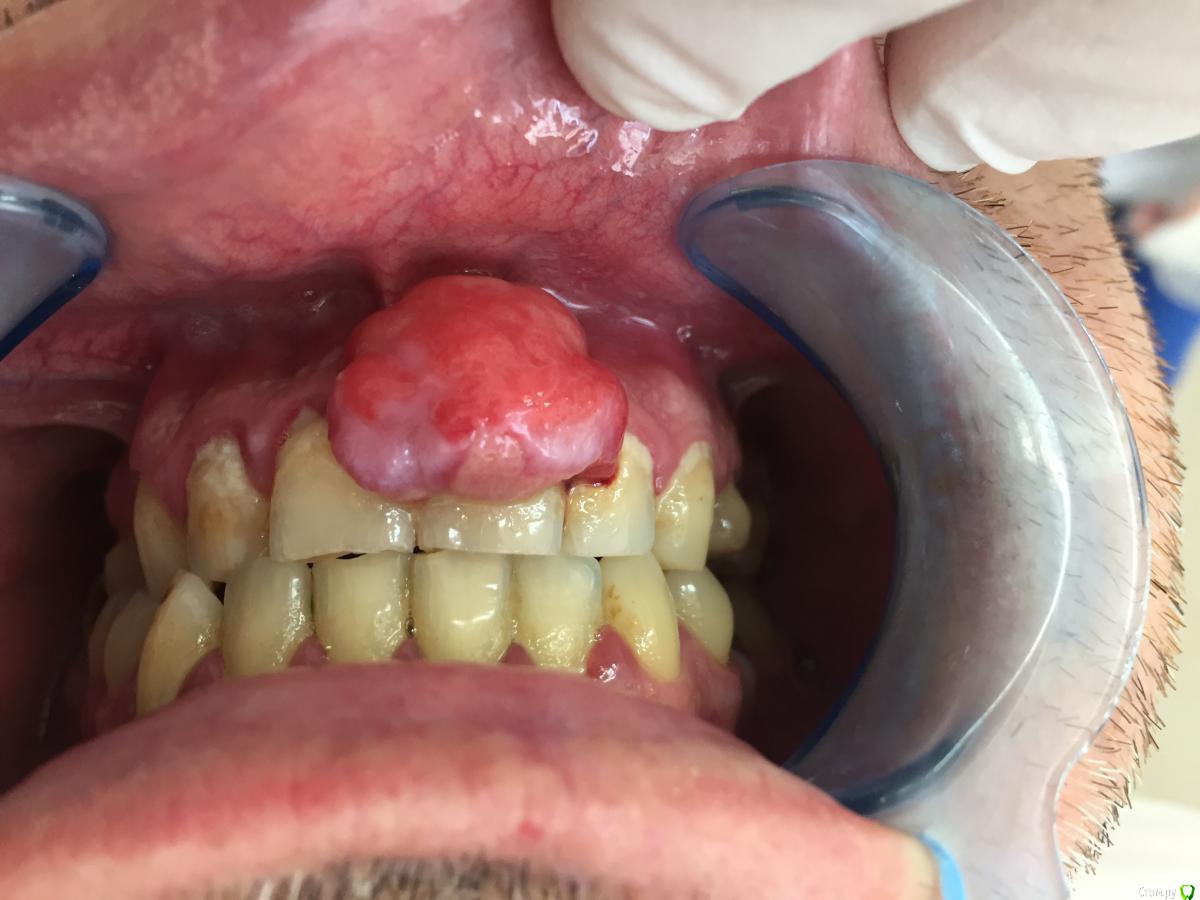

dr.i Опубликовано 9 июня, 2018 Поделиться Опубликовано 9 июня, 2018 (изменено) Пациент обратился с жалобами на дискомфорт из за размеров этого образования,болей нет только иногда кровоточит,говорит что это у него более 10-ти лет,до этого размеры были маленькие и не беспокоили его а за последние пол года начало увеличиватся.Какова будет ваша тактика ?Я сам решил просто рассечь и удалить эту гадость но честно говоря смушают размеры и плюс случай такой первый раз лишний опыт не помешал бы.Спасибо. Изменено 9 июня, 2018 пользователем dr.i Ссылка на комментарий

AndyAndy Опубликовано 9 июня, 2018 Поделиться Опубликовано 9 июня, 2018 Гигиену он, видимо, тоже больше 10 лет назад делал... я за эпулис. Приподнимали его, «ножку» видели какую-то? 2 Ссылка на комментарий

dr.i Опубликовано 9 июня, 2018 Автор Поделиться Опубликовано 9 июня, 2018 Гигиену он, видимо, тоже больше 10 лет назад делал... я за эпулис. Приподнимали его, «ножку» видели какую-то?Я постарался приподнять ,было похожее на ножку но из за размеров и плотной консистенции сложно было все разглядет. Ссылка на комментарий

red_butler Опубликовано 9 июня, 2018 Поделиться Опубликовано 9 июня, 2018 Голосую за эпулис 2 Ссылка на комментарий

Дмитрий Л. Опубликовано 9 июня, 2018 Поделиться Опубликовано 9 июня, 2018 Я сам решил просто рассечь и удалить эту гадость но честно говоря смушают размеры и плюс случай такой первый раз лишний опыт не помешал бы.Спасибо.Научить чистить зубы.Рассекать смысла большого нет, может сильно кровить.Высечь до кости, бором или фрезой обработать +- милиметр кортикалки и под йодоформным тампоном провести.Гистология.Эндодонтия 21. 2 Ссылка на комментарий